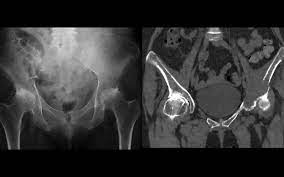

} myeloma cells produce paraproteins which are found in blood and urine (protein bence jones). The pelvis contains numerous lytic lesions without reactive sclerosis which have multiple myeloma. Healthy plasma cells help you fight infections by making antibodies that recognize and attack germs. Spotlight revised international staging system for multiple myeloma: Multiple myeloma is a cancer of plasma cells, which are white blood cells found mainly in the bone marrow. If you still can't find it, please let us know so we can add it!. Other tests include blood monoclonal immunoglobulin and radiology tests to determine the extent of bone lesions. Multiple myeloma is the second most common type of blood cancer after leukemia. 1,2,3 it accounts for approximately 1% of all malignant. Treatment response, detection of relapse. International myeloma working group molecular classification of multiple myeloma: It accounts for approximately 10% of all. Extraosseous myeloma refers to any manifestation of multiple myeloma where there is plasma cell proliferation outside the atypical manifestations of multiple myeloma: